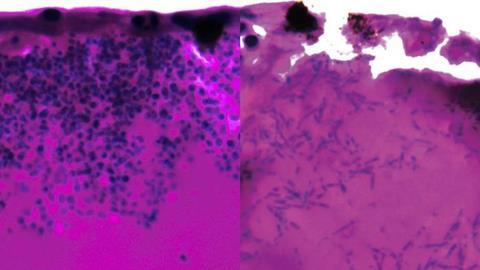

Above image shows Candida auris filaments during infection stage. Image Credit: University of Exeter.[/caption] Genes reveal potential vulnerabilities

The researchers discovered that Candida auris can form elongated fungal filaments, possibly to search for nutrients. They also identified which genes are switched on and off during infection, highlighting potential vulnerabilities. Several genes activated during infection code for nutrient pumps that scavenge for iron and draw it into the fungal cells.